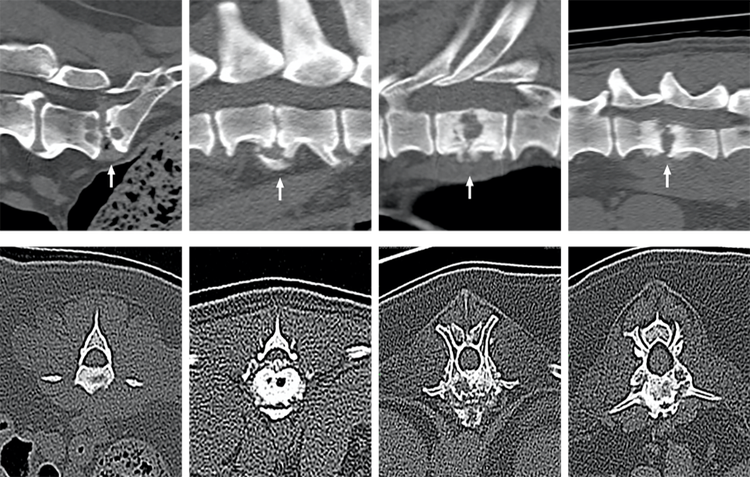

To date, MRI has been the imaging modality of choice, with consistent CT imaging features of Discospondylitis in dogs and cats not previously reported in detail. However, with the increased availability of CT in clinical practice, the research set out to examine CT features that could support the diagnosis of Discospondylitis.

Gomes, SA, Targett, M, Lowrie, M. Computed tomography features of discospondylitis in dogs. J Vet Intern Med. 2022; 36( 6): 2123- 2131.  https://doi.org/10.1111/jvim.16551